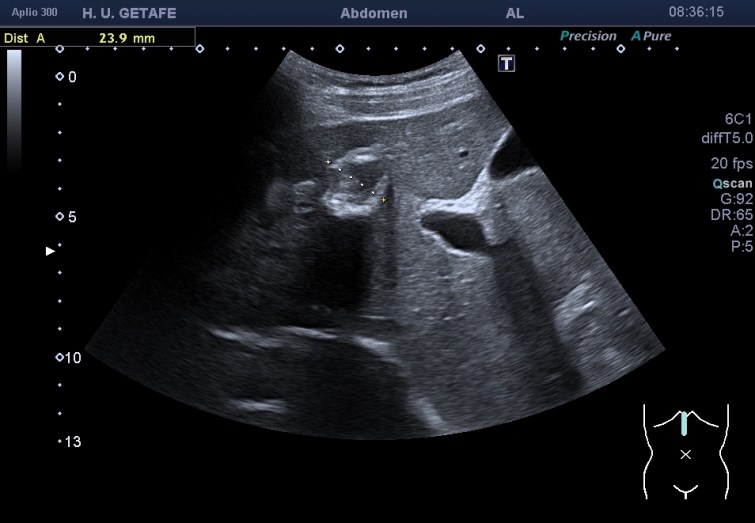

Durante la exploración de una eco de abdomen en el contexto de un paciente que acude por elevación de transaminasas observo una imagen heterogénea, irregular, con una pared marcadamente calcificada, bilobulada de gran tamaño que medí en dos partes ya que me pareció claramente que estaban diferenciadas.

Una de ellas, la primera, era mucho más hiperecogénica y más pequeña, su centro estaba mas calcificado, su sombra acústica posterior era mucho más acuciada y llamaba más la atención. Justo al lado, otra lesión de mayor tamaño, su calcificación era mucho más sutil y más periférica delimitando una LOE hipoecogénica de un tamaño muy importante, adyacente a la más pequeña, como he comentado previamente. Ambas sin señal Doppler.